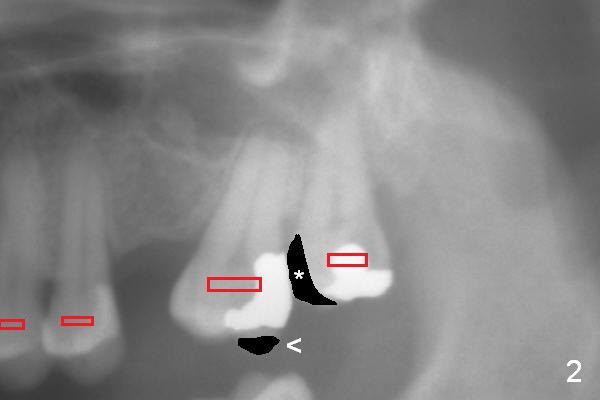

A second option for #14 is segmental orthodontic treatment. Initially keep the tooth #16 and mesial reduction (Fig.2 *). Place brackets between #11 and 16 (Fig.3 red) and open coil spring between #13 and 15.

When the tooth #15 is distalized (Fig.3), place an implant at #14 (Fig.4 green), parallel to the tooth #13 and extract #16 (black). When the implant osteointegrates, place an abutment (Fig.5 pink), provisional (white) and bracket at #14. The implant is used as an anchorage to further distalize #15 until the latter reaches the normal position (Fig.6). CT study shows how much the tooth movement is needed prior to implantation.